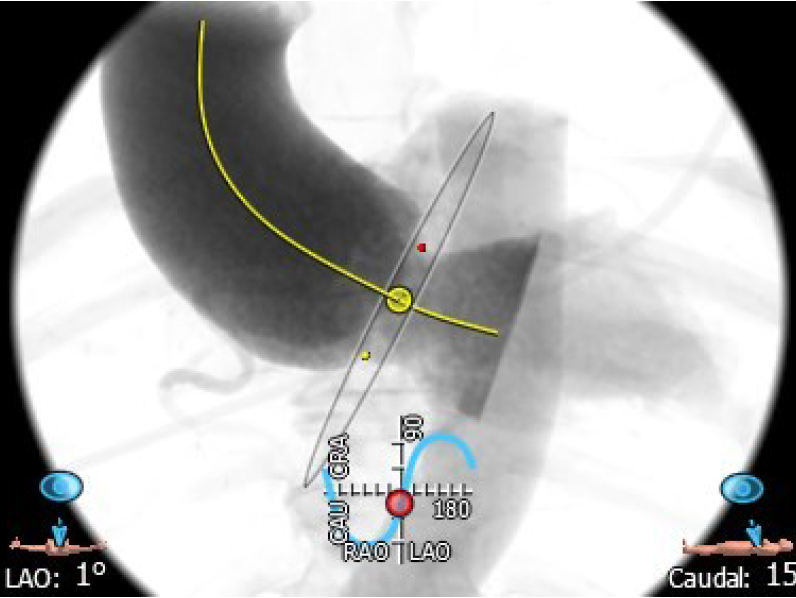

4.患者术中造影角度LAO:1°,CAU:15°。

术中DSA参考投照角度:LAO 1°,Caudal 15°

主动脉瓣环平面水平夹角65°